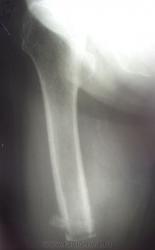

Помогите интерпретировать снимки. Женщине 73 года, в августе 2010 ампутация по поводу гангрены стопы, сахарный диабет. Около недели гнойное отделяемое из рубца, со слов.

В приёмном отделении, местный статус: отёка культи нет; свищ в области постеоперационного рубца, на момент осмотра отделяемого нет; гиперемии кожи культи нет.

Осмотр хирурга гнойного отделения: состояние удовлетворительное. В области п/о рубца участок гипергрануляции 0.5х0.5 см, отёка культи нет. Рубец - без признаков воспаления.

Поступила сегодня, результатов анализов еще нет. Поставила остеомиелит, но у меня впечатление, что на спил одет какой-то колпачок, но я ни разу такого не видела. Может, кому встречалось подобное?

Остеомиелит дистального конца культи.

ничего не имею против остеомиелита. Я его и поставила. Мне не ясен четкий, как по линеечке, ровный нижний контур и треугольная плотная тень с ровными контурами по наружному краю. Применяется ли какой-то колпачок на спил? Потому что у меня сомнение, что на самом дистальном краю - именно костная ткань...

Читаем Рейнберга: "Наиболее типичными для культи являются так называемые венечные, коронарные секвестры (рис. 115). Венечный остеонекроз имеет вид кольца или в более редких случаях - довольно высокого цилиндра. Он охватывает то всю кость по окружности, то только часть диафизарного цилиндра. Иногда венечный остеонекроз имеет форму воронки, образующейся из внутренних или внешних слоев коркового вещества."

Можете посмотреть http://v-ugnivenko.narod.ru/Rh/2-4.html - один в один

Коллега, или я чего-нибудь не понял или ошибка вкралась, но вы писали, что была ампутация стопы, а видим культю бедра(?)...

"...в августе 2010 ампутация на уровне средней трети бедра по поводу гангрены стопы, сахарный диабет" - пропустила в начале ветки.